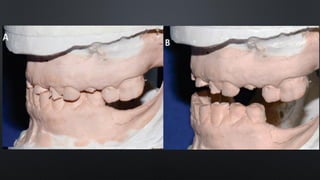

FORMA DOS ARCOS

• TRIANGULAR (EM V): ESTREITA NO SEGMENTO ANTERIOR E COM

DIVERGÊNCIA NOS SEGMENTOS POSTERIORES

• OVÓIDE: RELATIVA CURVATURA DO SEGMENTO ANTERIOR COM LEVE

CONVERGÊNCIA DOS SEGMENTOS POSTERIORES

• QUADRADA (EM U): SEGMENTO ANTERIOR PRATICAMENTE RETO E

SEGMENTOS POSTERIORES PARALELOS

• PARABÓLICA: SEGMENTOANTERIOR CURVADO COM LEVE DIVERGÊNCIA DOS SEGMENTOS POSTERIORES FORMA DOS ARCOS

• TRIANGULAR (EMV): ESTREITA NO SEGMENTO ANTERIOR E COM DIVERGÊNCIA NOS SEGMENTOS POSTERIORES FORMA DOS ARCOS

• OVÓIDE: RELATIVACURVATURA DO SEGMENTO ANTERIOR COM LEVE CONVERGÊNCIA DOS SEGMENTOS POSTERIORES FORMA DOS ARCOS

• QUADRADA (EMU): SEGMENTO ANTERIOR PRATICAMENTE RETO E SEGMENTOS POSTERIORES PARALELOS FORMA DOS ARCOS